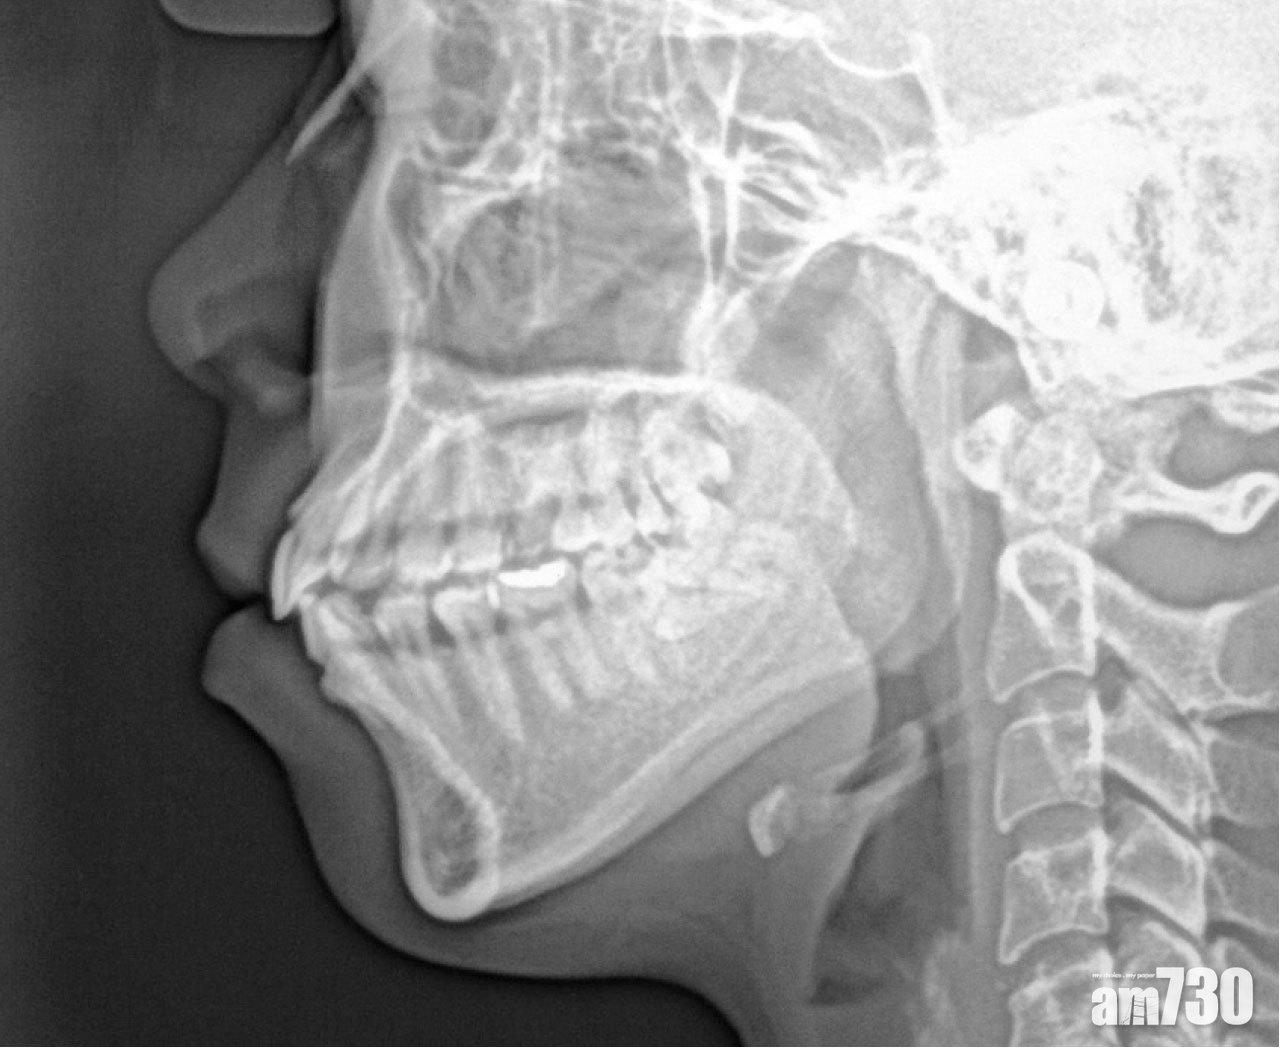

上回說了關於視覺錯覺的故事,解釋了X光片上白色的部分其實是透明。牙套、種牙螺絲、牙橋、活動牙托等含有金屬,放在口腔裡影X光固然會阻擋輻射,形成菲林上的白色部分。除此以外,如果菲林的一角在口中屈曲,包裝在其背面的鉛箔會翻到前頭,阻擋輻射,結果那角落就會呈白色了。與此同時,如果菲林和X光管對位不準確,菲林的部分位置就接收不到輻射,亦會呈白色(透明)。空白這概念的深厚底蘊,不但見於老子的《道德經》,也在心理學家「交白卷」的曠世奇作中。